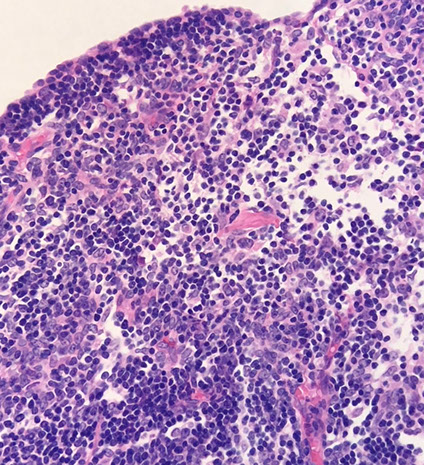

Micro: the normal lobular follicular architecture is preserved ad has normal thymic weight with increased lymphoid follicles with germinal centers in the interstitium and corticomedullary junction

- the epithelial component is inconspicuous

- there is no influx of reactive inflammatory cells